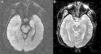

Hereby we present the clinical case of a seventy one year old female with dyslipidemia, hypothyroidism and breast ductal carcinoma with radical exeresis and treated with chemotherapy. She was admitted in the hospital following an event of sepsis due to methicillin-sensitive Staphylococcus aureus (due to reservoir infection). She suffers from progressive disorientation, repetitive talking, and sleepiness with progression towards status epilepticus, which is why she was admitted in the unit of intensive care medicine (ICM). The urgent cranial computed tomography (CT) scan performed did not show any significant findings. At admission her state is post-critical after the administration of intravenous (IV) benzodiazepines and her temperature is 38°C; the rest of the device based-medical examination was normal. The blood sample showed platelet levels of 22×109/l, creatinine levels of 3.5mg/dl, urea levels of 95mg/dl, C-reactive protein (CRP) levels of 15.6mg/dl, the rest being normal. Doctors proceeded with orotracheal intubation and lumbar puncture (LP) followed by secretion of cerebrospinal fluid (CSF) colourless at normal-pressure without cells, glucose levels of 68mg/gl and protein levels of 64mg/dl (plasma proteins 5.2g/dl). Doctors proceeded with sedoanalgesia, fluid therapy, levetiracetam, and broad-spectrum IV antimicrobial treatment including acyclovir. They were isolated in bronchoaspiration and one hemoculture of the extended-spectrum-beta-lactamase-producing Klebsiella pneumonia without condensation in the chest X-ray was collected; both the urine culture and the CSF culture tested negative. CSF with polymerase chain reaction (PCR) for herpes simplex virus (HSV), cytomegalovirus (CMV), varicella zoster virus (VZV) and Epstein–Barr virus (EBV) all tested negative, and the cytology to rule out malignant cells tested negative too. Serologies for human immunodeficiency virus (HIV), hepatitis, HSV, CMV and VZV tested negative for active infections. Elevated CA 125 level (180.3U/ml); remaining tumour markers normal. Negative test results for the anti-DNA antibodies, antinuclear antibodies, c-ANCA and p-ANCA. Thyroid hormones in normal ranges with replacement therapy and negative test results for the antiperoxidase and antithyroglobulin antibodies. One second CT scan with the administration contrast is performed and it rules out structural disease, and also another control LP with secretion of colourless fluid at normal pressure with normal biochemical profile without cells, and negative for malignancy. Given the low level of consciousness, one electroencephalogram (EEG) is performed that is consistent with the effects of sedation and the nuclear magnetic resonance (NMR) of the brain with the following results: in the T2-weighted sequence of the hypocampic region, there is hyperintensity of left predominance, in the diffusion-weighted sequence, there is hyperintensity and a mild decrease of the apparent diffusion coefficient (ADC) in the hypocampic region of the left temporal lobe. After the administration of paramagnetic contrast there is no presence of any uptakes (Figs. 1 and 2A and B).

The clinical manifestations of LE are the subacute2 appearance of several neuropsychiatric alterations including, among others, cognitive impairment, seizures, depression, irritability, hallucinations, and loss of short term memory.3,4 In most cases, the CSF5 shows inflammatory changes with discrete proteinorrachia and/or pleocytosis without pathognomonic findings. The CT scan5 is usually normal, without contrast uptake, while in 70% of the cases, the NMR of the brain5 is asymmetrically hyperintense in both temporal lobes, especially the T2 and the FLAIR-weighted sequences, while remains unenhanced after the administration of contrast. The EEG can show temporal or diffuse slowness, temporal spikes, and temporal or generalized focal seizure activity.